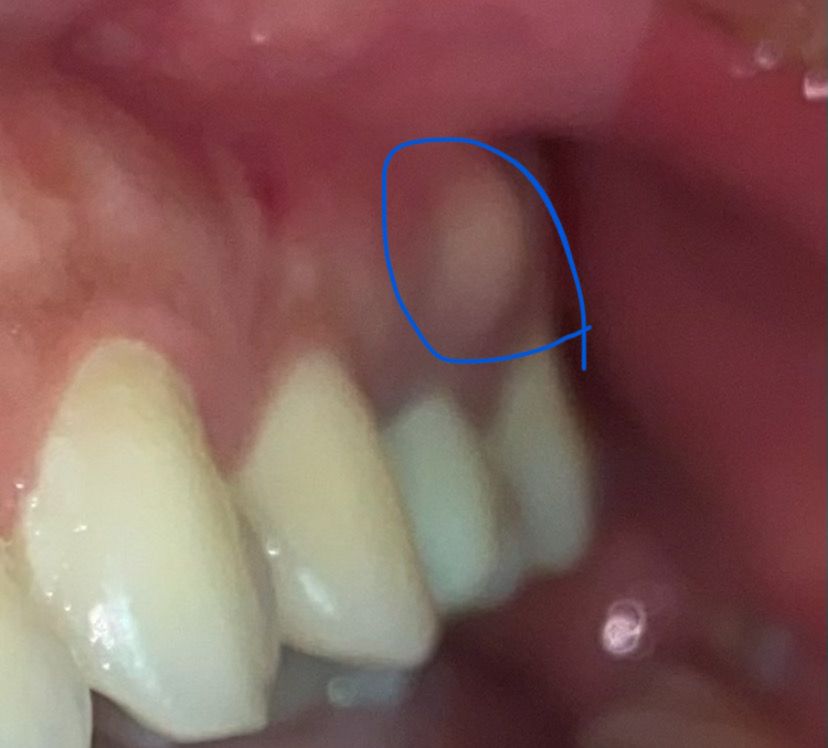

작년 하반기에 신경치료 한 치아에 염증이 생겼는데 첫번째 사진이 막 시작되었을 때라 사진 상에서는 많이 작은데 이후로 커졌다가 들어갔다가 자기 혼자 반복하더라구요...? 다니던 치과에서는 임플란트 하자고 했고 다른 치과 가 본 결과 신경이 하나 남아있다고 재신경치료 말씀하셔서 3월에 예약 잡았다가 일이 너무 바빠서 취소하고 아직 치료하지 못하고 있습니다 ㅠㅠ 뭔가 튀어나온 게 없어서 또 들어갔구나~ 했는데 혀로 뭔가 움직여져서(?) 보니까 밑으로 염증이 늘어진... 느낌으로 생겼는데 이게 많이 악화된 상태인지 궁금합니다... 9월에야 치료할 수 있는데 염증이 악화되면 재신경치료도 못할 수 있는 건지 걱정도 되구요. 그렇다면 재신경치료는 나중에 하더라도 염증만 먼저 어떻게 잡을 방법이 없을지도 궁금합니다... ㅠㅠ 답변 부탁 드릴게요 감사합니다

치아 뿌리 끝에 염증이 있게 되면 사진처럼 잇몸이 부울수 있습니다.